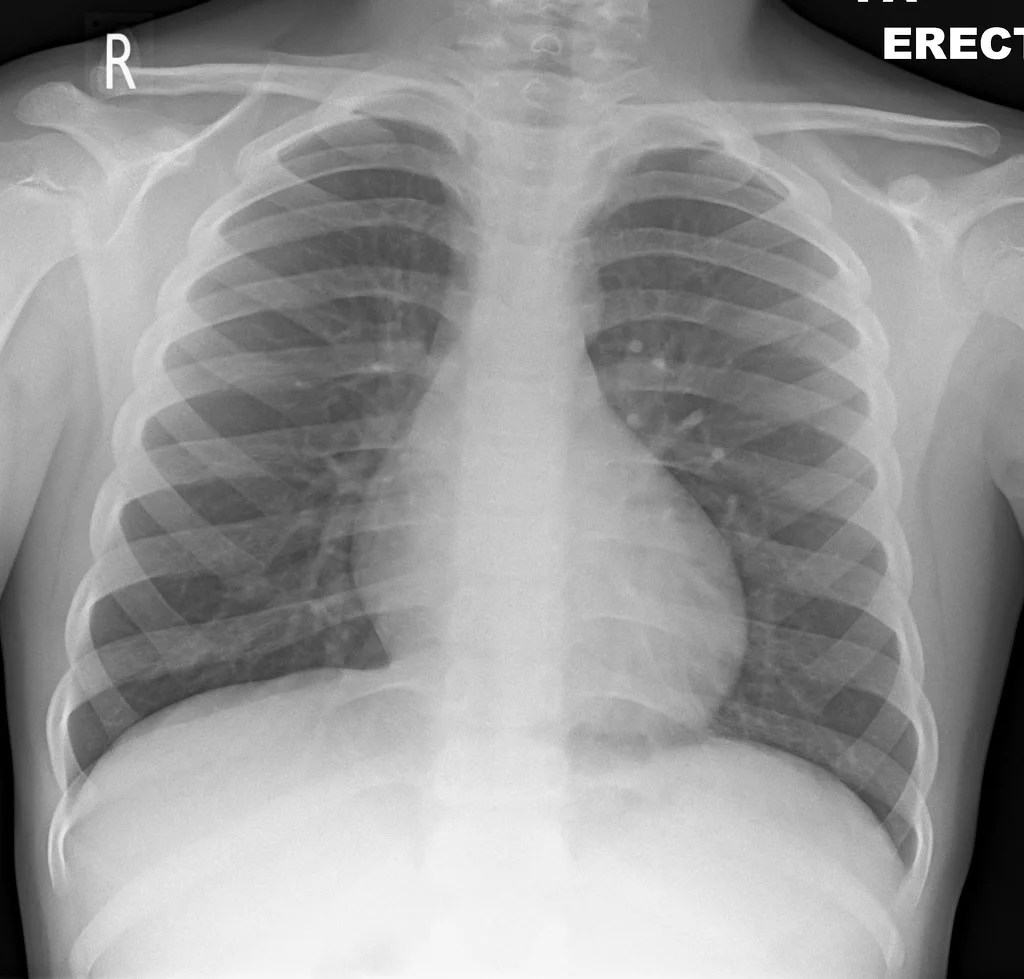

Colección 162 Healthy Normal Man Chest X Ray Fresco. The heart is not enlarged; It is almost always the first imaging study ordered to evaluate for pathologies of the thorax , although further diagnostic imaging, laboratory tests, and additional physical examinations may be necessary to help confirm the diagnosis. Large • 2180 × 2660 pixels. There is a degree of hyperinflation as evidenced by both increased retrosternal airspace and somewhat flattened and depressed diaphragms. Click image to align with top of page.

3d illustration human lungs isolated on black background. Tap on/off image to show/hide findings. The heart is not enlarged; 7.3 × 8.9 in • 300 dpi • jpeg. There is a degree of hyperinflation as evidenced by both increased retrosternal airspace and somewhat flattened and depressed diaphragms. Chest xray normal healthy man show stock photo (edit now) 452114047. Plus, get full access to … Front view human lungs isolated on black background. Hover on/off image to show/hide findings.. Chest xray normal healthy man show stock photo (edit now) 452114047.